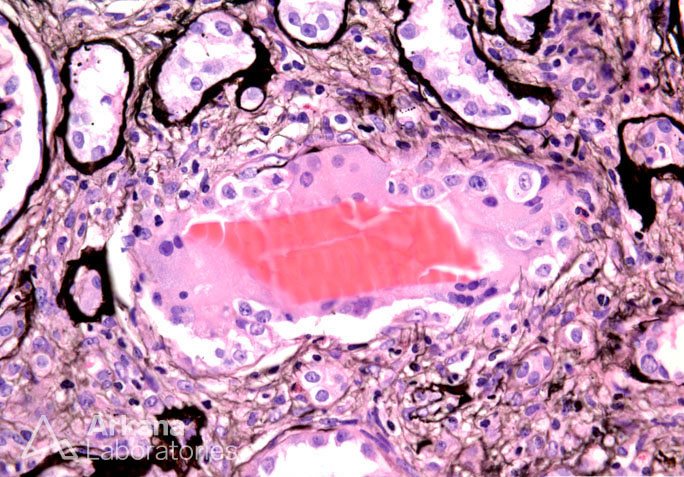

Light Chain Cast with Cellular Reaction on Silver Stain_2